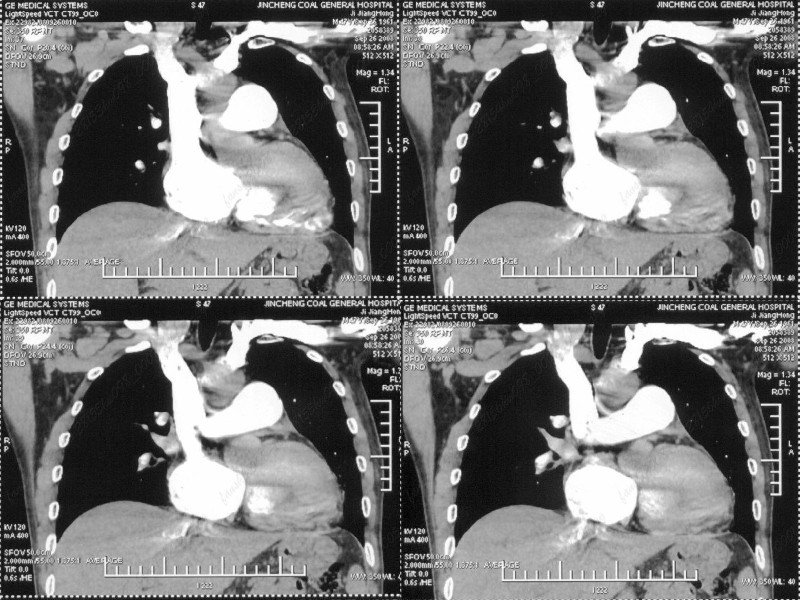

男性,47岁。胸部不适一年,ct检查发现右胸膜下结节。http://www.radida.com/bbs/forum.php?mod=viewthread&tid=46094

图像很清,资料很全。工作做的很细,向您学习!观阁下的强化图像发现,您们强化后扫描时间挺早,延迟时间大约在16—18秒之间吧。估计目的是为了观察肺动脉及分支的情况。但现有的资料并不能提示动脉栓塞改变。建议楼主可在机器上仔细观察,或许会有异常发现。另外,个人感觉右侧应为肺内结节而非胸膜结节。考虑肺内良性小结节,炎性假瘤可能性大。

汇报临床诊断:右肺动脉分枝栓塞

右肺静脉充盈缺损,左心房体积小,右肺动脉远端动脉充盈缺损,右肺血管影细小,考虑;右肺动脉远端栓塞.